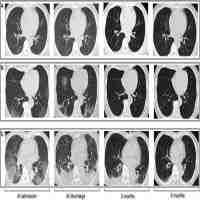

| Description | Journal: Ultrasound in Medicine & Biology There is growing evidence regarding chest X-ray and computed tomography (CT) findings for coronavirus disease 2019 (COVID-19). At present, the role of lung ultrasonography (LUS) has yet to be explored. The main purpose of this study was to evaluate the correlation between LUS findings and chest CT in patients confirmed to have (positive reverse transcription polymerase chain reaction [RT-PCR]) or clinically highly suspected of having (dyspnea, fever, myasthenia, gastrointestinal symptoms, dry cough, ageusia or anosmia) COVID-19. This prospective study was carried out in the emergency department, where patients confirmed of having or clinically highly suspected of having COVID-19 were recruited and underwent chest CT and concurrent LUS exam. An experienced emergency department physician performed the LUS exam blind to the clinical history and results of the CT scan, which were reviewed by two radiologists in consensus for signs compatible with COVID-19 (bilateral ground-glass opacities in peripheral distribution). A compatible LUS exam was considered a bilateral pattern of B-lines, irregular pleural line and subpleural consolidations. Between March and April 2020, 51 patients were consecutively enrolled. The indication for CT was a negative or indeterminate RT-PCR test (49.0%) followed by suspicion of pulmonary embolism (41.2%). Radiologic signs compatible with COVID-19 were present in 37 patients (72.5%) on CT scan and 40 patients (78.4%) on LUS exam. The presence of LUS findings was correlated with a positive CT scan suggestive of COVID-19 (odds ratio: 13.3, 95% confidence interval: 4.5–39.6, p < 0.001) with a sensitivity of 100.0%, specificity of 78.6%, positive predictive value of 92.5% and negative predictive value of 100.0%. There was no missed diagnosis of COVID-19 with LUS compared with CT in our cohort. The correlation between LUS score and CT total severity score was good (intraclass correlation coefficient: 0.803, 95% confidence interval: 0.60–0.90, p < 0.001). LUS exhibited similar accuracy compared with chest CT in the detection of lung abnormalities in COVID-19 patients. |